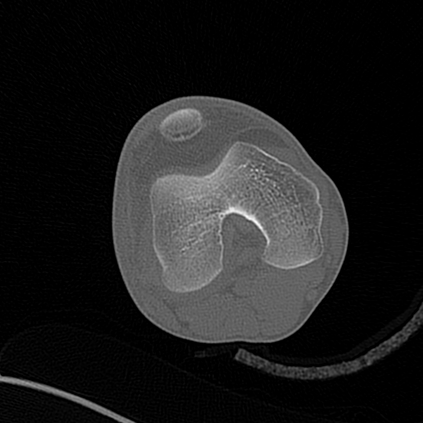

CT reconstruction provides radiologists with images for diagnosis and treatment, yet current deep learning methods are typically limited to specific anatomies and datasets, hindering generalization ability to unseen anatomies and lesions. To address this, we introduce the Multi-Organ medical image REconstruction (MORE) dataset, comprising CT scans across 9 diverse anatomies with 15 lesion types. This dataset serves two key purposes: (1) enabling robust training of deep learning models on extensive, heterogeneous data, and (2) facilitating rigorous evaluation of model generalization for CT reconstruction. We further establish a strong baseline solution that outperforms prior approaches under these challenging conditions. Our results demonstrate that: (1) a comprehensive dataset helps improve the generalization capability of models, and (2) optimization-based methods offer enhanced robustness for unseen anatomies. The MORE dataset is freely accessible under CC-BY-NC 4.0 at our project page https://more-med.github.io/